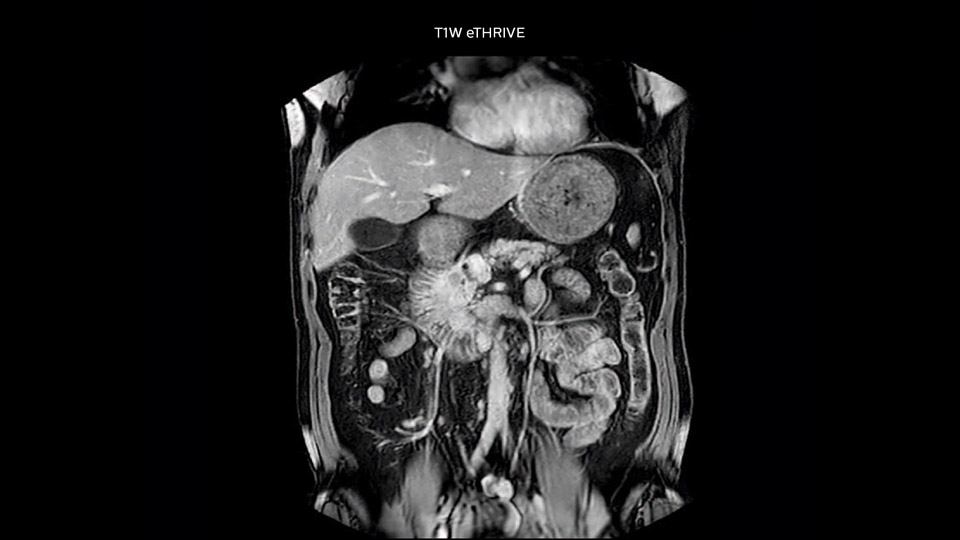

“We include mDIXON for the dynamic sequences because of the robust and homogeneous fat suppression we get with that. We had been using eTHRIVE, but we are now quite happy with mDIXON. Sometimes we use a medication to calm the bowels, to further improve the image quality.”